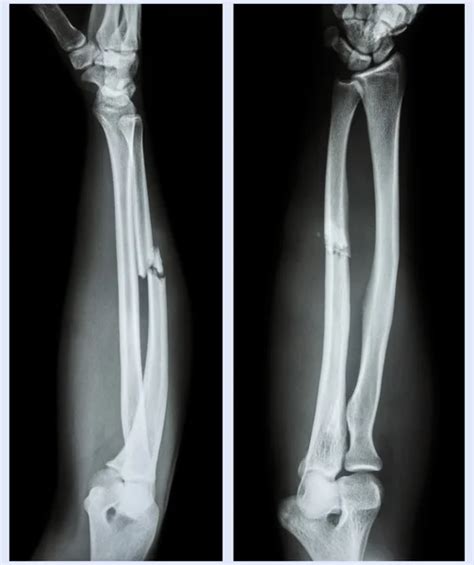

Cas de syndrome d'impaction ulnaire, causé par l'excès de longueur du cubitus et de la styloïde ulnaire, qui entrent en collision avec la région carpienne. Look through examples of artère ulnaire translation in sentences, listen to pronunciation and learn grammar. Definition from wiktionary, the free dictionary

Cas De Syndrome D'impaction Ulnaire, Causé Par L'excès De Longueur Du Cubitus Et De La Styloïde Ulnaire, Qui Entrent En Collision Avec La Région Carpienne.